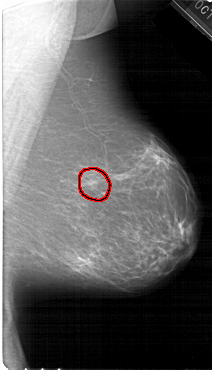

A_1381_1.LEFT_CC

FILE: A_1381_1.RIGHT_MLO.OVERLAY

TOTAL_ABNORMALITIES 1

ABNORMALITY 1

LESION_TYPE MASS SHAPE OVAL MARGINS ILL_DEFINED

ASSESSMENT 4

SUBTLETY 3

PATHOLOGY BENIGN

TOTAL_OUTLINES 1

BOUNDARY